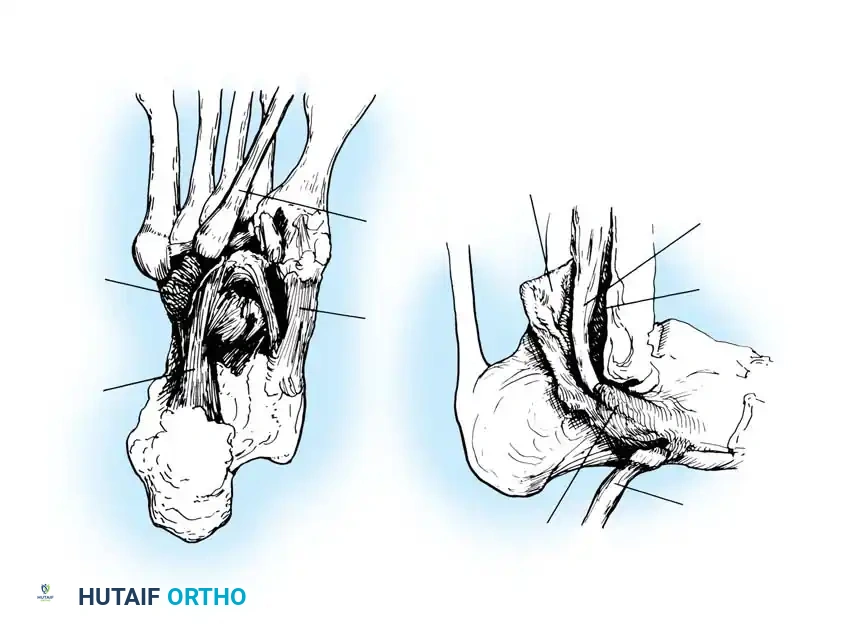

Disorders of the peroneal tendons represent a complex spectrum of pathology that can cause significant lateral hindfoot pain, instability, and functional impairment. The peroneus longus and peroneus brevis tendons are critical dynamic stabilizers of the lateral ankle and primary evertors of the foot. The peroneus brevis inserts onto the base of the fifth metatarsal, while the peroneus longus courses through the cuboid groove to insert onto the plantar aspect of the medial cuneiform and the base of the first metatarsal, acting as a vital plantarflexor of the first ray.

Pathology within this tendon complex is frequently misdiagnosed as chronic lateral ankle sprains. A thorough understanding of the regional anatomy, biomechanics, and associated osseous deformities—particularly the cavovarus foot—is essential for the orthopedic surgeon to formulate an effective treatment algorithm.

2. Peroneal Tendinitis with Instability

The second type involves tendinitis associated with instability of the peroneal tendons at the level of the superior peroneal retinaculum (SPR). This may occur with or without an acute rupture or avulsion of the SPR. It is highly correlated with chronic lateral ankle instability and is frequently seen in younger athletes following acute inversion or dorsiflexion trauma. The incompetence of the SPR allows the tendons to subluxate anteriorly over the fibula, leading to mechanical attrition and longitudinal split tears, predominantly of the peroneus brevis.

3. Stenosing Tenosynovitis of the Peroneus Longus

The third variant is stenosing tenosynovitis specifically affecting the peroneus longus tendon. This is often associated with distinct anatomical anomalies, including:

* A painful or hypertrophic os peroneum.

* An enlarged peroneal tubercle on the lateral calcaneus.

* Pathological changes at the calcaneocuboid joint.

* Complete encasement of the peroneus longus tendon within a bony tunnel at the level of the cuboid.

Carefully evaluate the septum that extends from the fibula to the SPR, separating the peroneus longus and brevis. An accessory peroneal tendon (peroneus quartus) may be present in a separate compartment, contributing to overcrowding and stenosis. Release this septum and inspect the peroneus brevis, looking for any accessory slips.